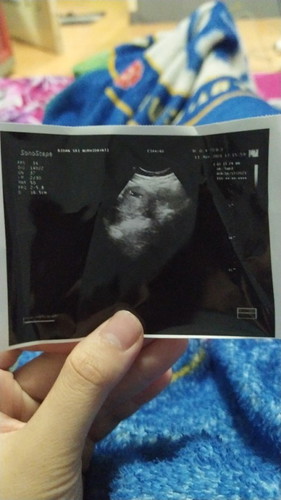

USG 9 minggu belum ada janin nya

Bunda bunda, kemarin sore saya USG di bidan. Ini ke 2 kali nya saya periksa. Sebelumnya pertama kali periksa di bidan yang berbeda, dan waktu itu cuma di hitung sudah berapa week dari tanggal pertama haid terakhir. Saat pertama diperiksa awal bulan maret kata bidan baru 5 minggu. Dan harusnya sekarang sudah 9 minggu. Tapi kata bidan kemarin saya USG, dia ngotot kalo kehamilan saya baru 6 mingguan karna ternyata baru ada kantong kehamilan nya saja itupun masih kecil banget. Gimana ya bunda bunda saya bingung😌 sedih rasanya. Apakah kehamilan saya gak berkembang atau gimana saya gangerti:(#seriusnanya #bantusharing #firstbaby #jangandibully #ingintahu